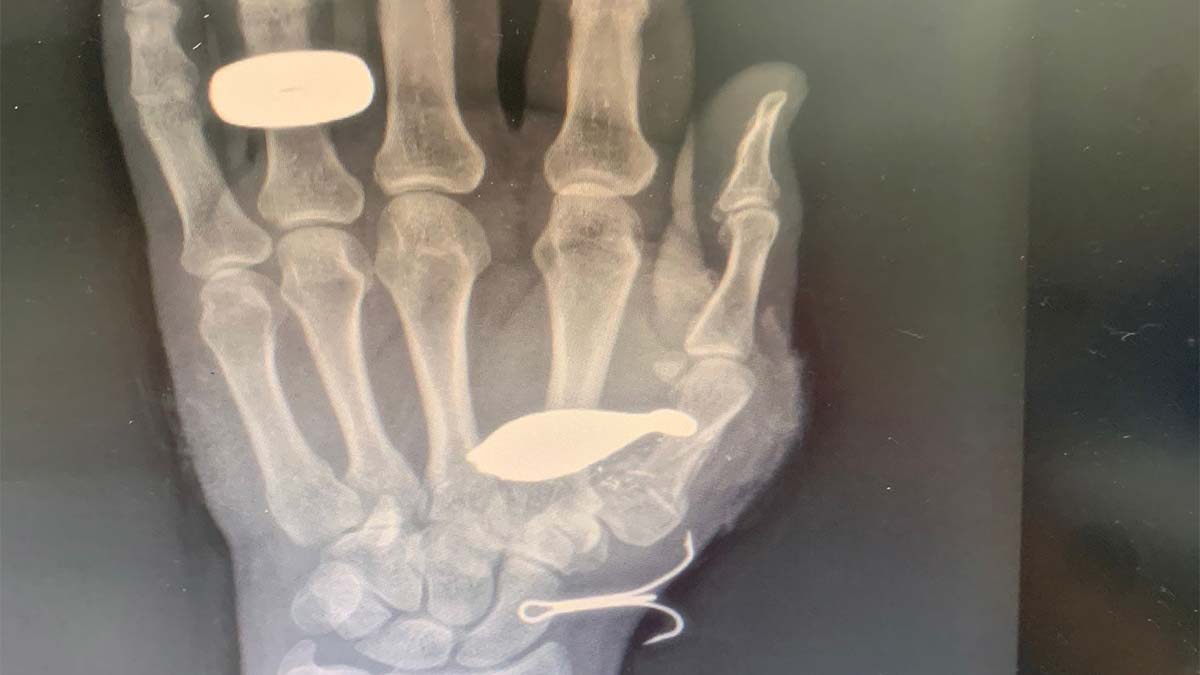

Büyükçekmece sahilinde 20 Ağustos Cumartesi günü akşam 21.00 sıralarında balık tutmaya giden Engin Çağlayan’ın oltası denizin içinde takılı kaldı. Çağlayan oltayı sıkıştığı yerden çıkartmak için çekerken, misina koptu. Oltanın ucundaki balık kurşunu fırlayarak Çağlayan’ın eline saplandı. Elinden kanlar akan Çağlayan, ambulansla hastaneye gitti. Çapa Tıp Fakültesi Hastanesi’nde çekilen el röntgeninde balık kurşununun kemiğe saplandığı belirlendi. Ameliyat olan Çağlayan’ın başparmağında kalıcı hasar oluşabileceği belirtildi.

Balık kurşunuyla yaralandığına kimseyi inandıramadığını söyleyen Engin Çağlayan, “Oltayı başındaki kurşunla birlikte denize attım. Olta takılınca misinayı çekmeye başladım. 15 metre kadar çektim, sonra misina koptu. Balık kurşunu fırlayarak elime saplandı. Kan fışkırdı, bacanağım ilk müdahaleyi yaptı. Ambulansla hastaneye gittim, yaklaşık 3 saat sürdü. Tekrar ameliyat olacağım. Başparmağımın eklemleri parçalandığı için, ameliyatla demir takacaklar. Enteresan bir durum. Kim sorsa anlatıyorum, ultrason görüntüsü görene kadar, inanmıyorlar. Kalıcı bir hasar olup olmayacağı ameliyattan sonra belli olacak. Bu saatten sonra balık tutmam. İnsanlara olta takılınca misinayı çekmek yerine, kesmelerini tavsiye ediyorum” dedi.